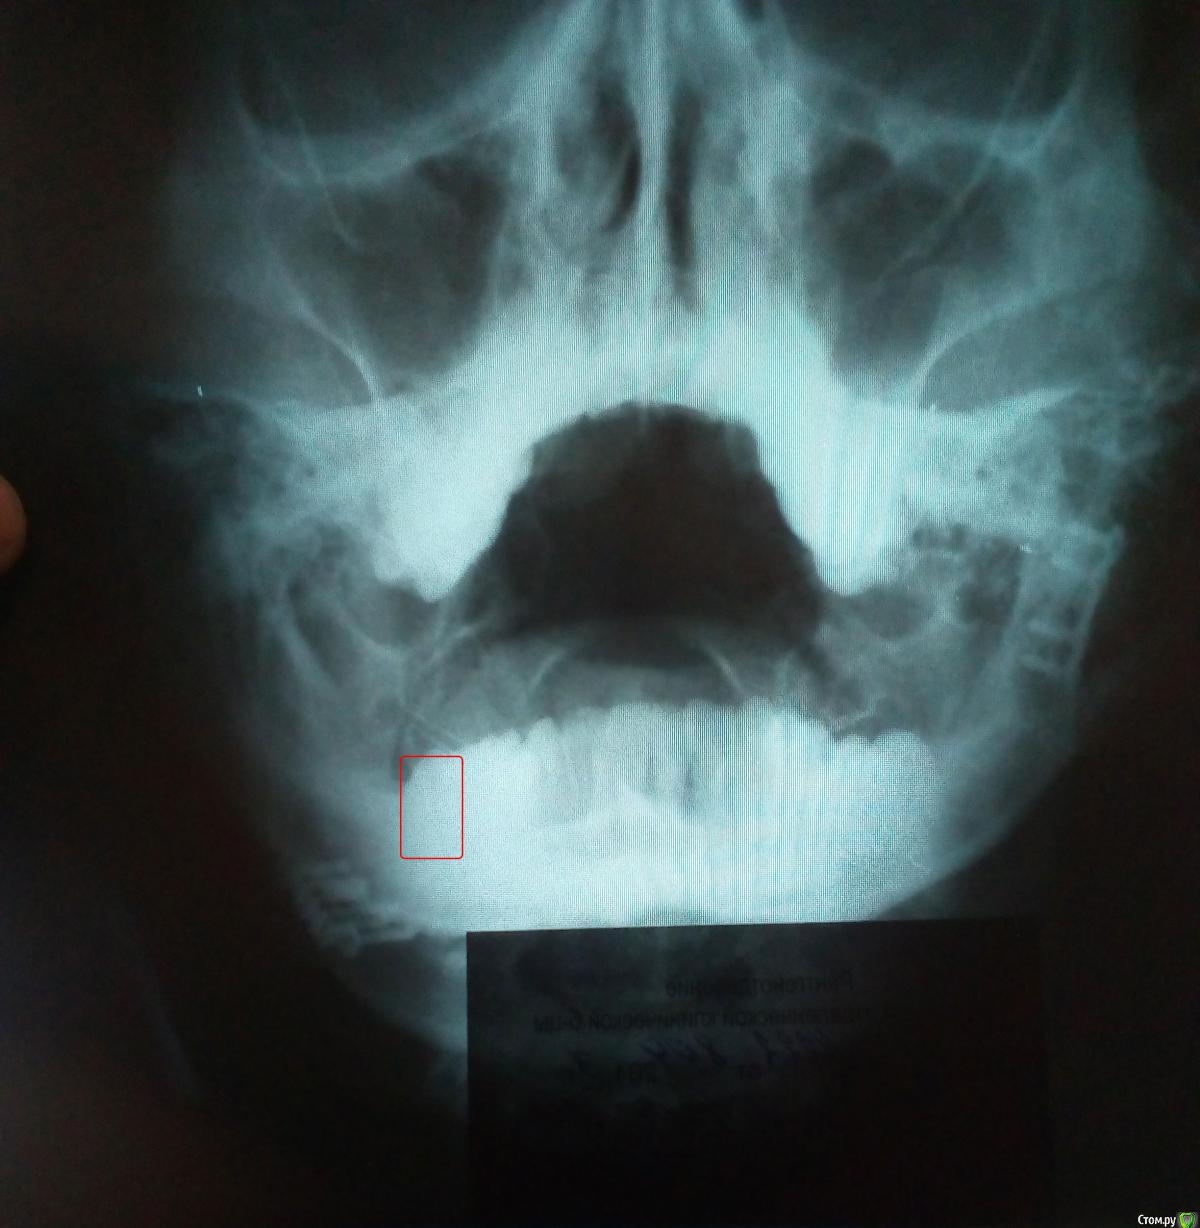

R3AD Опубликовано 13 ноября, 2019 Автор Поделиться Опубликовано 13 ноября, 2019 (изменено) Красным отметил зубы для удаления 2 шт. Как сказал хирург, челюсть была сломана с отходом осколков. Изменено 13 ноября, 2019 пользователем R3AD Ссылка на комментарий

red_butler Опубликовано 14 ноября, 2019 Поделиться Опубликовано 14 ноября, 2019 Этот снимок не информативен Ссылка на комментарий

Irouil Опубликовано 14 ноября, 2019 Поделиться Опубликовано 14 ноября, 2019 Судя по этому снимку, Вы рискуете переломом при удалении зубов в равной степени, как и до удаления. Лучше предоставить оптг Ссылка на комментарий